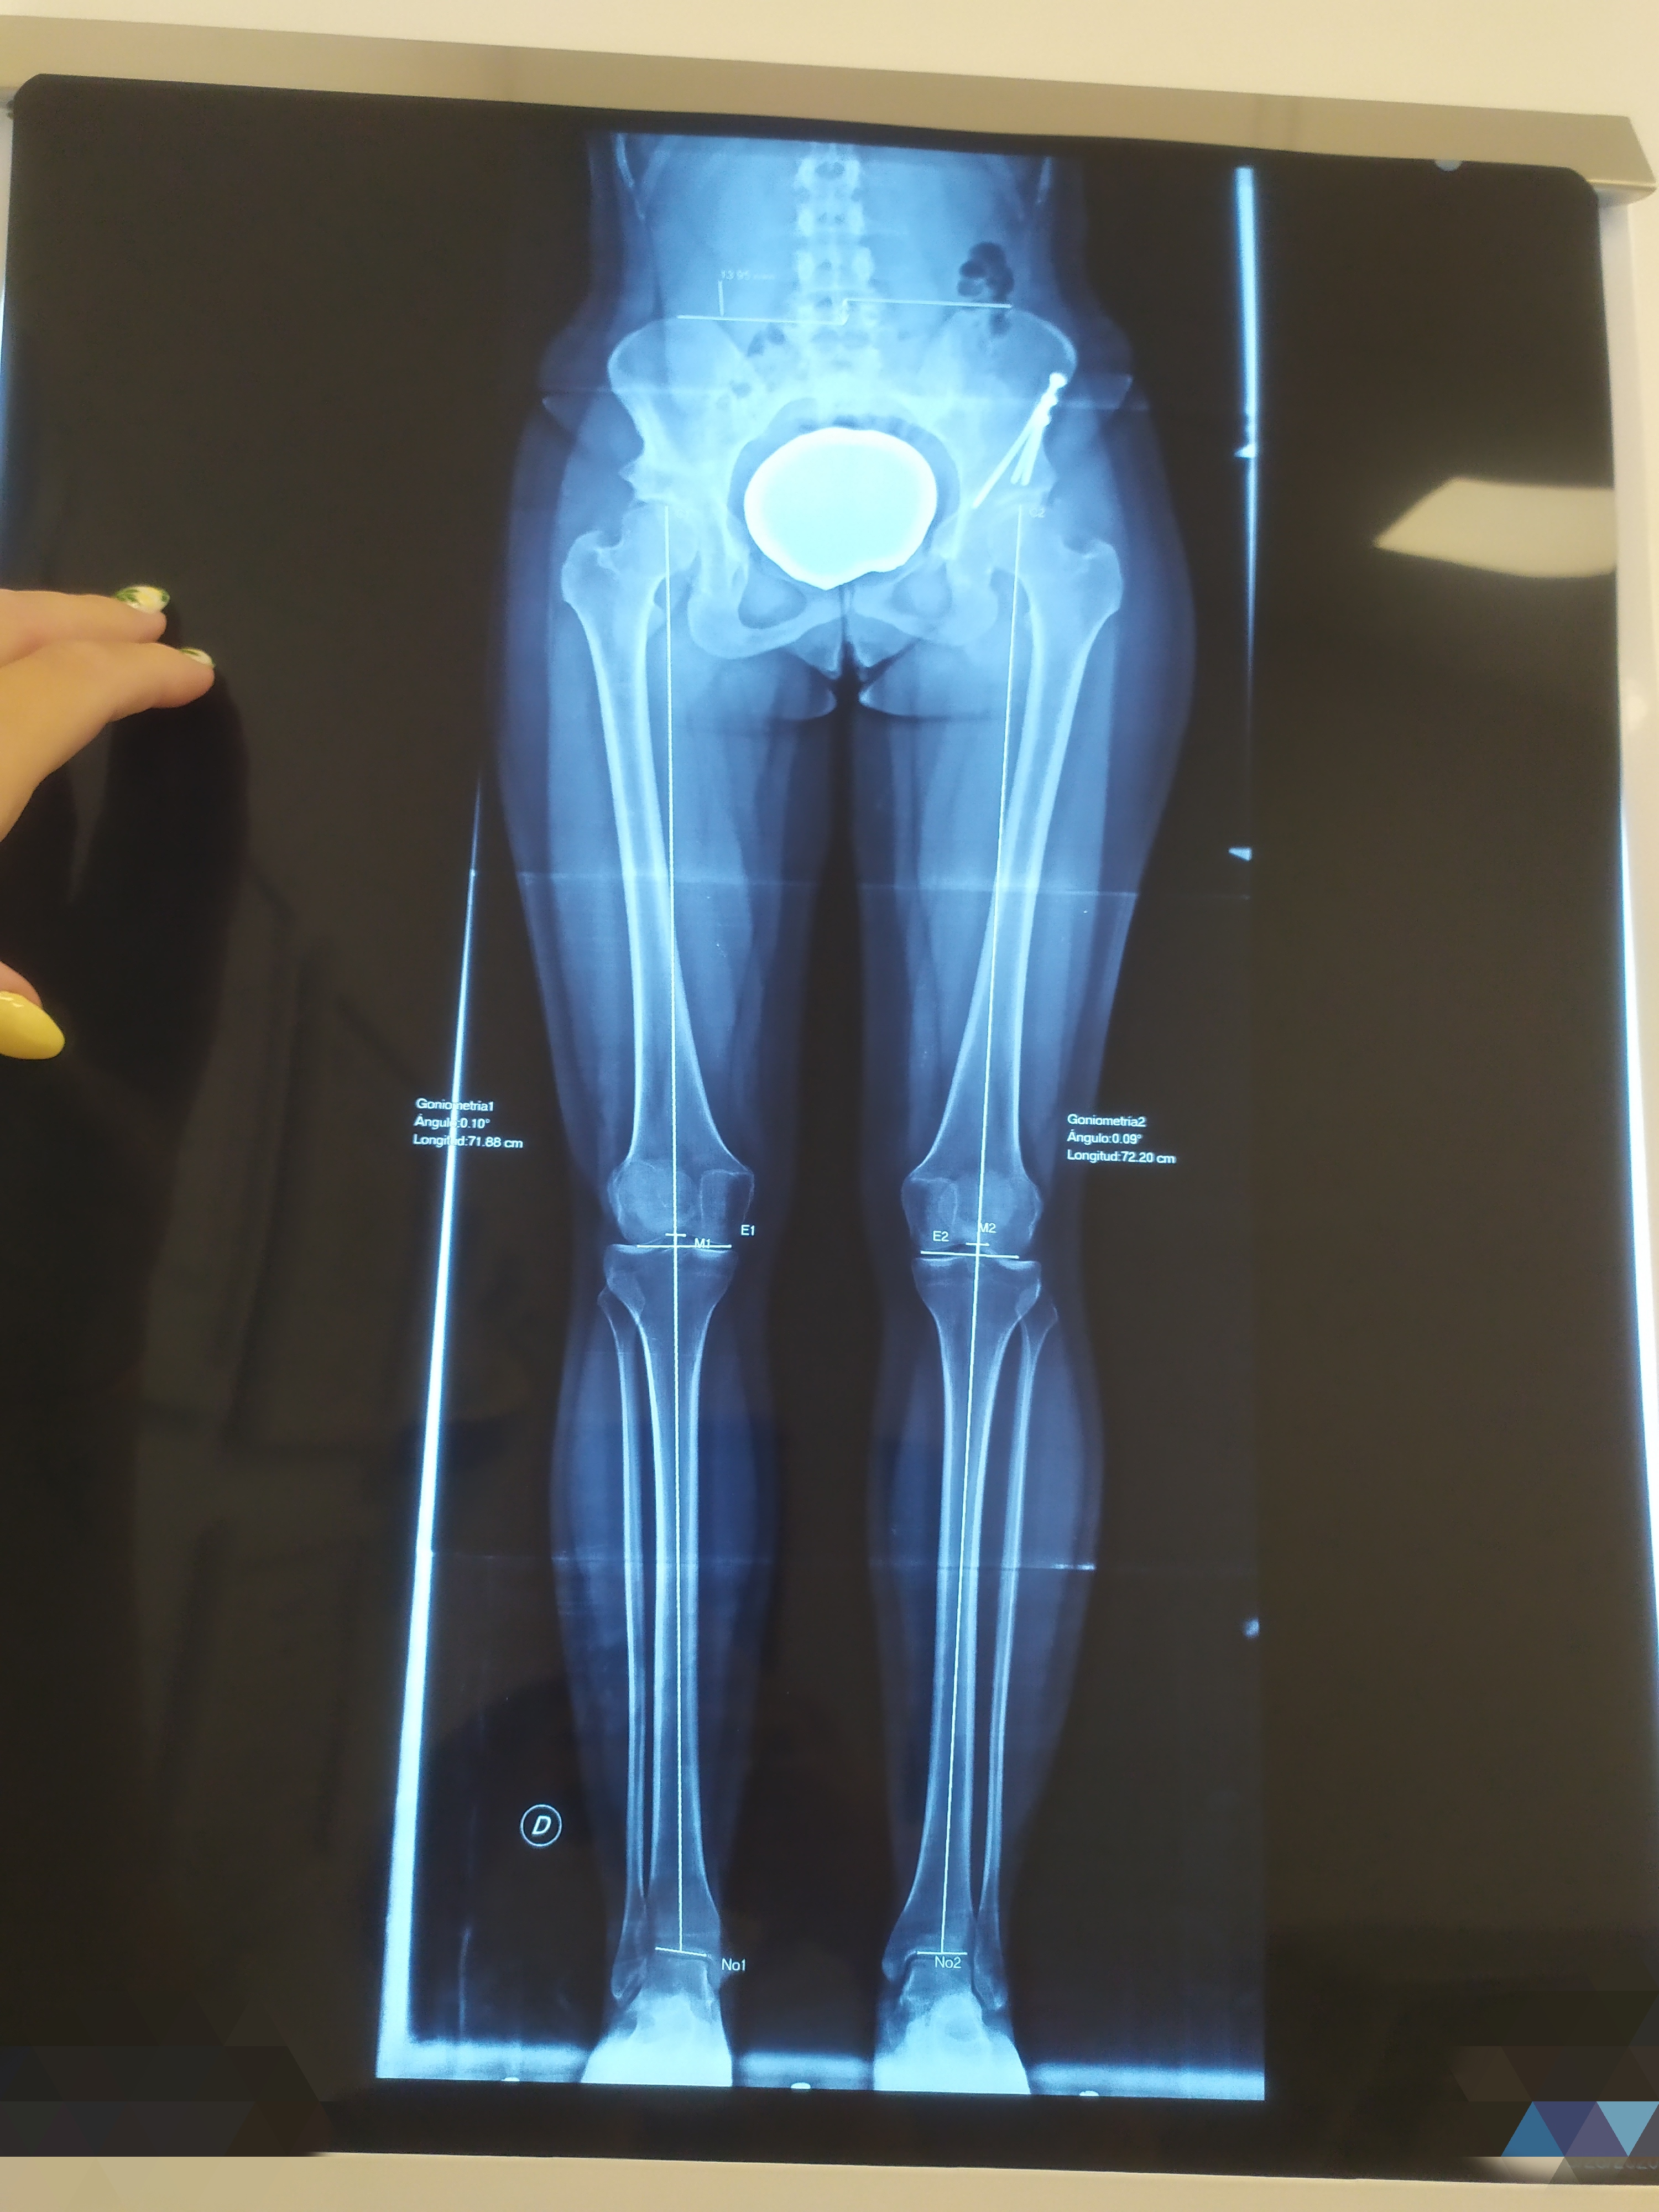

Decidieron hacerme una radiografía de medición de miembros y efectivamente, salía lo que pensábamos todos. Tengo una pierna un poco más larga que la otra. No es algo que se note a leguas, pero sí algo que me ha provocado un pinzamiento en la L4 y L5 y probablemente por lo que la primera operada, que es la pierna más corta, me duela.

Voy a dejaros por aquí las imágenes de la Rx.